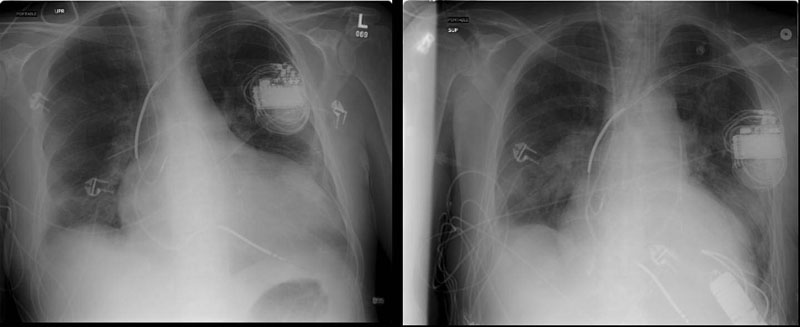

Figure 9: Pre- and postoperative chest radiographs in a 6’7” male demonstrating ventricular decompression.

- Some will argue that the output of continuous flow pumps like the Jarvik 2000 is inadequate for certain patients. Although intrathoracic placement of the Heartmate pump has been described [9], pump size limits this approach to larger patients. The Jarvik 2000 has provided reliable and sufficient outputs for all of our patients (Figure 9 is a pre and postoperative CXR showing LV decompression in a patient that was 6’7” with a body surface area of nearly 2.3). That said, the Jarvik 2000 is an assist, and not replacement device.